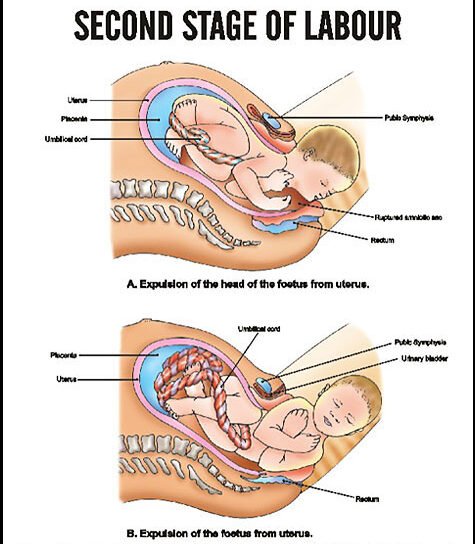

The second stage begins with the complete dilation of the cervix and ends with the expulsion of the fetus. This stage is concerned with the descent and delivery of the fetus through the birth canal. Second stage has two phase:

10. Delivery of head is done by extension in between contractions of uterus with guard over the perineum

11. Following delivery of the head, mouth and nose are cleaned

12. After delivery of anterior shoulder posterior shoulder is delivered by drawing the baby’s head in upward direction towards the mother’s abdomen

13. Then trunk is delivered by lateral flexion